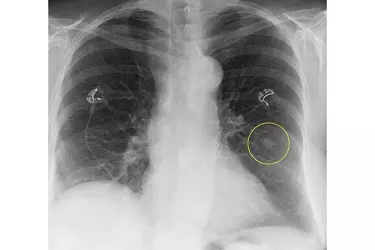

Digital X-Ray through DR is used for getting high resolution images of Chest, Joints, Abdomen, Bones, PNS and other body organs. The quality of Digital Radiography images is so high that it is comparable to most CT Scan images. The radiation dose used in Digital Radiography is much lesser than the Conventional X-Ray or the CR System.

X-Ray is an excellent diagnostic modality to diagnose any kind of bone fractures or joint pain. X-Ray of the chest is done to diagnose pneumonia or other lung diseases. X-Ray of the KUB region is done to diagnose stones in the kidneys or the ureter. X-Ray of the abdomen is done to diagnose any kind of perforation in the intestine. X-Ray of the knee joint gives valuable information about the joint spaces and the cartilage in patients suffering from knee joint pain. X-Ray of the spine is done to diagnose the causes of back pain and to detect any deformity in the spine.